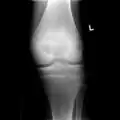

A variety of imaging studies can be used to diagnose chondroblastoma, with radiographs being the most common.[10][8] Laboratory studies are not considered useful.[14] Classical chondroblastoma (appearing on long bones) appears as a well-defined eccentric oval or round lytic lesion that usually involves the adjacent bone cortex without periosteal reaction.[10][13] A sclerotic margin can be seen in some cases.[10][13] For long bone chondroblastomas the tumor is typically contained to the epiphysis or apophysis but may extend through the epiphyseal plate.[10][13] Chondroblastomas are usually located in the medullary portion of bones and can, in some cases, include the metaphysis.[10][13] However, true metaphyseal chondroblastomas are rare and are typically the result of an extension from a neighboring epiphyseal legion.[10][13] Most lesions are less than 4 cm.[10] A mottled appearance on the radiograph is not atypical and indicates areas of calcification which is commonly associated with skeletally immature patients.[10] Additionally, one-third of all cases involve aneurysmal bone cysts which are thought to be the result of stress, trauma or hemorrhage.[10] In cases involving older patients or flat bones, typical radiographic presentation is not as common and may mimic aggressive processes.[10][13]